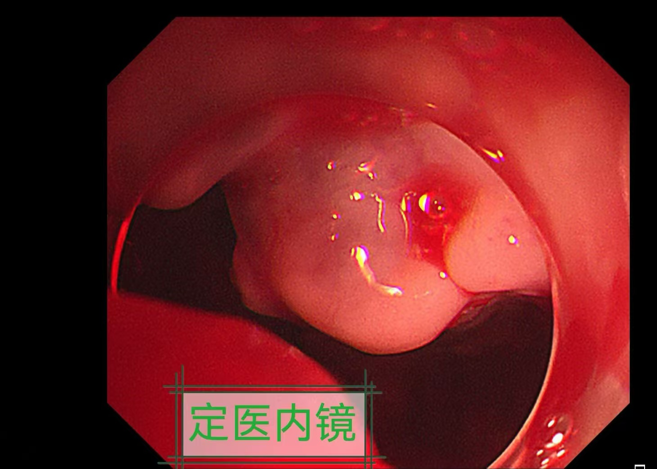

近日,我院多学科团队紧密协作,成功抢救一名81岁食管癌破裂大出血患者。患者高龄且基础状况差,经紧急救治后已转危为安。

危急时刻,李亚兰主任果断启动多学科抢救流程。胸外科、麻醉科、ICU团队快速集结,麻醉科宁传卫主任团队精准调控生命体征,为内镜操作创造稳定条件;李亚兰主任在复杂镜下环境中精准定位破裂口,成功实施内镜下夹闭术,有效控制出血。